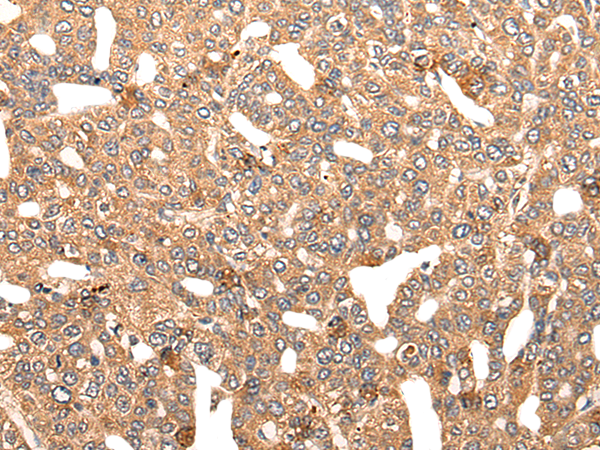

IHC positive control: |

Human colorectal cancer and human lung cancer |

IHC Recommend dilution: |

20-100 |